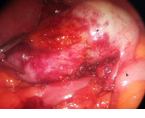

Κολονοσκόπηση. Ευδιάκριτα ευρήματα ισχαιμικής κολίτιδας (Ευγενική παραχώρηση Dr. V. Penopoulos)